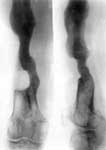

4.Результат лечения.